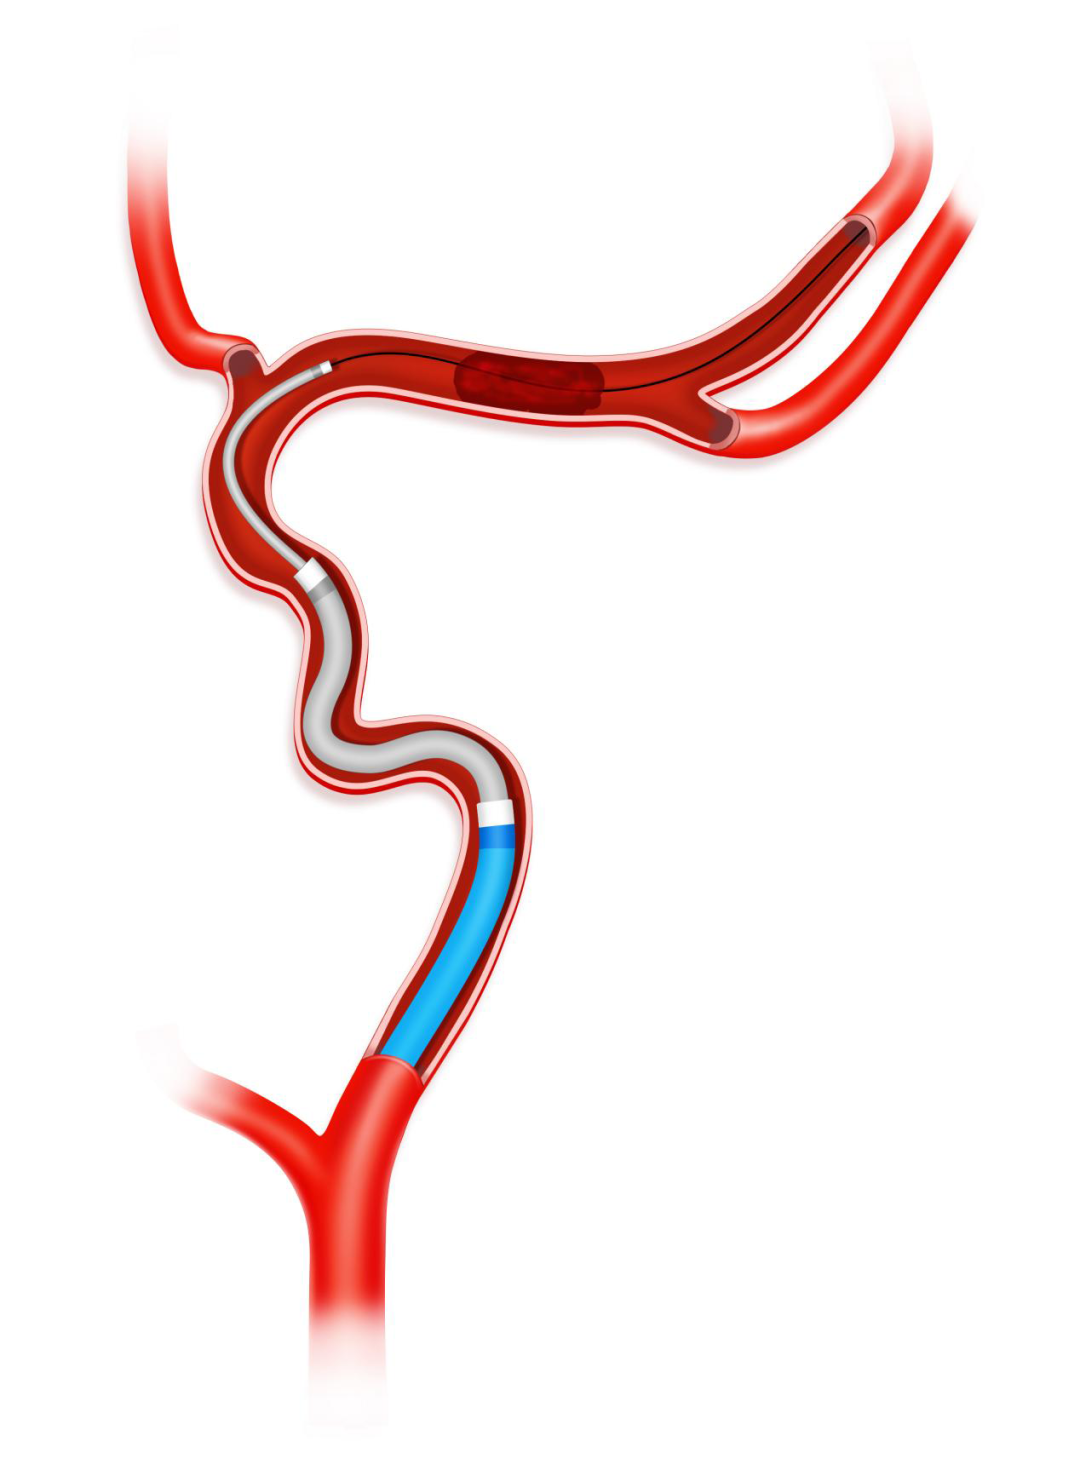

8F导引导管送至颈内动脉C1段中远端,Tethys AS®血栓抽吸导管到达颈内动脉C4段,0.014" 200cm 微导丝携17或者21系列微导管通过血管闭塞段。

撤出200cm微导丝,手推造影证实微导管末端到达闭塞段以远。

沿17或21系列微导管输送并释放3.0*25mm Syphonet®取栓支架,支架近段覆盖大脑中动脉闭塞病变部位,支架远端到达大脑中动脉M2。利用Syphonet®取栓支架的锚定作用和远端防血栓逃逸保护作用。